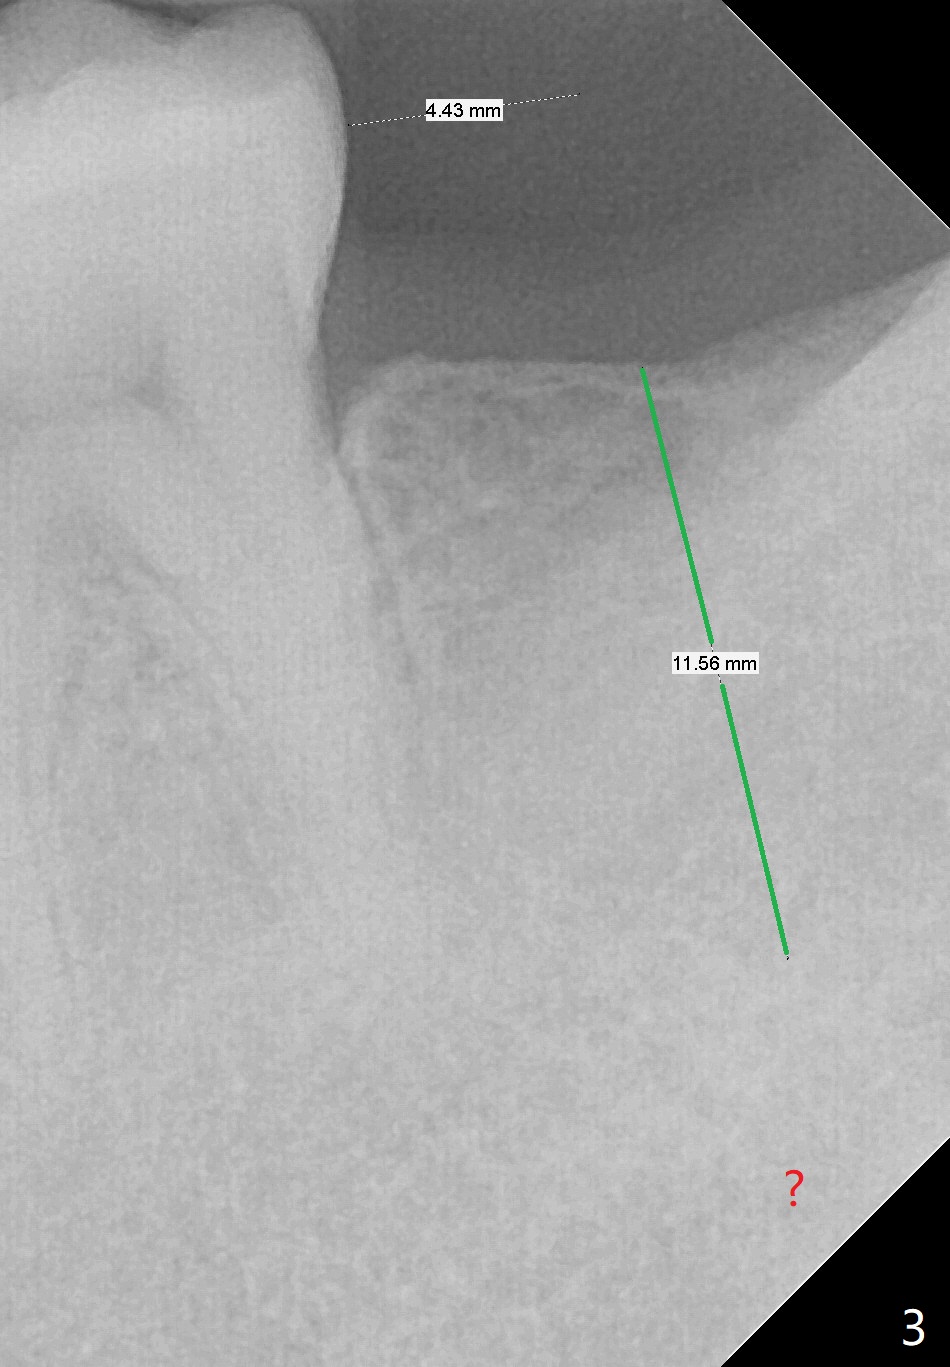

A 42-year-old man has lost #18 (due to 3rd molar impaction) for ~ 5 years (Fig.1). Because of the indistinct Inferior Alveolar Canal (Fig.3 ? vs. Fig.2 red dashed line), CBCT is taken for guided surgery (Fig.4: 5x11.5 mm).